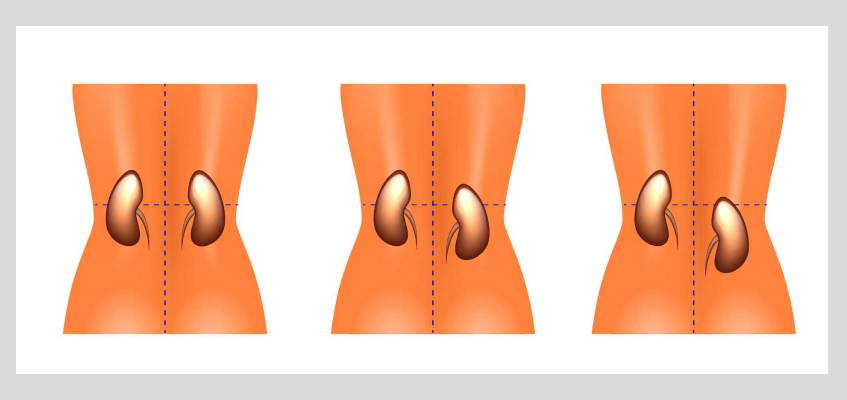

Опущение почки первой стадии означает смещение органа на величину от 1.5 позвонков (от 5 до 9 см). Это происходит только в вертикальном положении (когда человек стоит). В положении лежа почка занимает нормальное положение. Когда пациент лежит, орган возвращается в исходное место. Во время вдоха можно прощупать ее нижний полюс.

Опущение почки второй стадии означает умеренный нефроптоз. Почка опускается на величину двух и более позвонков на 2/3 своего размера и выходит из подреберья в положении стоя. Поддается ручному вправлению.

Опущение почки третьей стадии означает полный выход почки из-за линии ребер на величину от трех до пяти позвонков и опущение на уровень большого или малого таза.